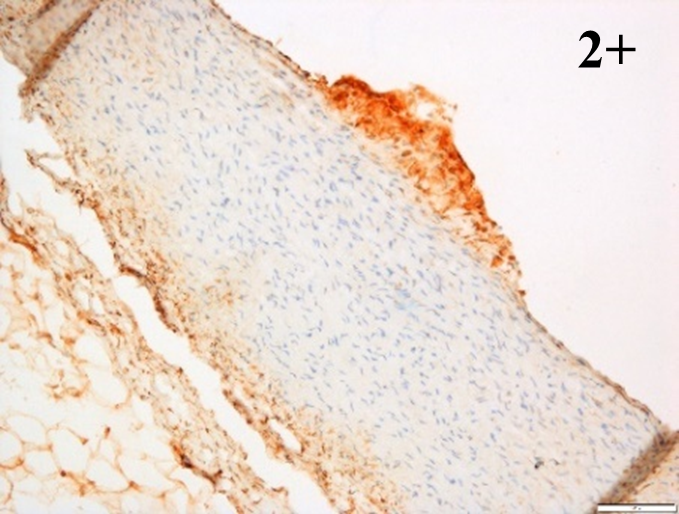

Immunoreactions of ICAM-1, VCAM-1, e-selectin, IL-6, IL-8, NF-

According to the percentage endothelial staining of cells, semi-quantitative

scores were applied. Score: 0 (negative); 1+ (1–10% positive cells); 2+

(11–25% positive cells) and 3+ (

Medium to high expressions of adhesion molecules, such as ICAM-1, VCAM-1 and

e-selectin were observed in the aortas of rabbits fed with HCD. This represents

the initiation of the lesion stage, where the endothelial cells have been

stimulated by the ox-LDL to express the adhesion molecules, which could lead to

the recruitment of monocytes and transmigrate into the intima by diapedesis as

well as differentiate into pro-atherogenic macrophages [47]. An increased

expression of pro-inflammatory biomarkers, such as IL-6, IL-8 and NF-